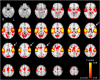

Materials and methods: fMRI data was acquired from 22 children with rolandic epilepsy and 22 age-matched controls (age range: 8-14 years), both at rest and using word-generation and reading tasks. Activation map analysis revealed no group differences (FWE-corrected, p < 0.05) and was therefore used to define regions of interest for pooled (patients and controls combined) language activation. Independent component analysis with dual regression was used to identify the sensorimotor resting-state network in all subjects. The associated functional connectivity maps were compared between groups at the regions of interest for language activation identified from the task data. In addition, neuropsychological language testing (Clinical Evaluation of Language Fundamentals, 4th edition) was performed.

Results: Functional connectivity with the sensorimotor network was reduced in patients compared to controls (p = 0.011) in the left inferior frontal gyrus, i.e. Broca's area as identified by the word-generation task. No aberrant functional connectivity values were found in the other regions of interest, nor were any associations found between functional connectivity and language performance. Neuropsychological testing confirmed language impairment in patients relative to controls (reductions in core language score, p = 0.03; language content index, p = 0.01; receptive language index, p = 0.005).

Conclusion: Reduced functional connectivity was demonstrated between the sensorimotor network and the left inferior frontal gyrus (Broca's area) in children with RE, which might link epileptiform activity/seizures originating from the sensorimotor cortex to language impairment, and is in line with the identified neuropsychological profile of anterior language dysfunction.